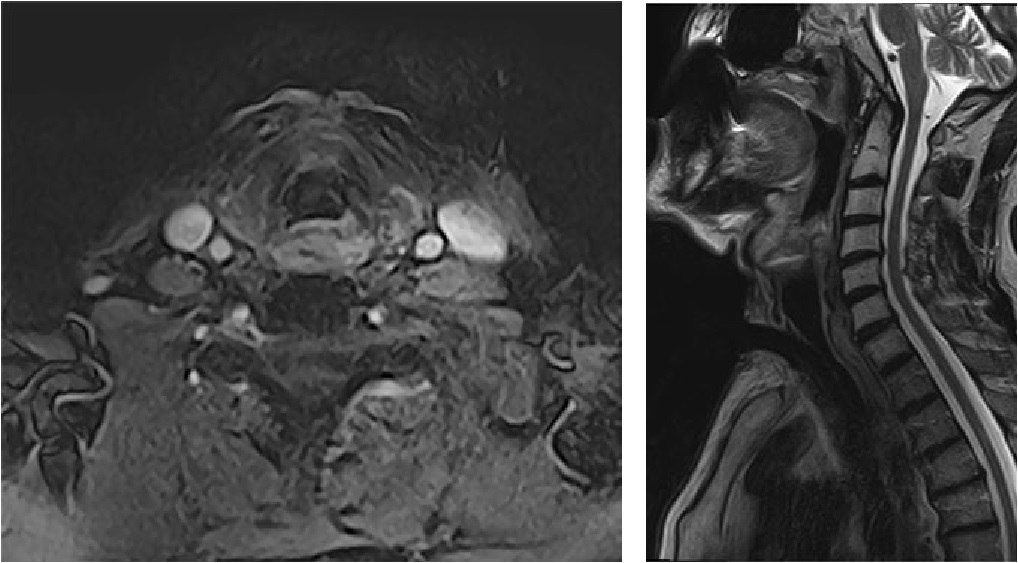

Patient N., aged 48 years, complained of impaired respiratory function, inability to swallow food, and loss of speech. Anamnesis revealed that in 2002, she was diagnosed with cancer of the folded section of the larynx T2N0M0. Condition after chemoradiotherapy. Progression in September 2018. During further examination, she was diagnosed with cancer of the laryngopharynx T2N0M0. Histologically, a squamous highly differentiated carcinoma was detected. Because of the development of clinical signs of acute respiratory failure, an emergency tracheostomy was performed in November 2018. Two courses of induction polychemotherapy were completed with negative dynamics. Computed tomography and endoscopic examination revealed that the tumor involved the laryngopharynx and cervical esophagus with complete obliteration of its lumen, with transition to the laryngeal posterior segments (Fig. 1).

Figure 1. MSCT image of the patient before surgery

Рисунок 1. МСКТ пациента перед операцией.